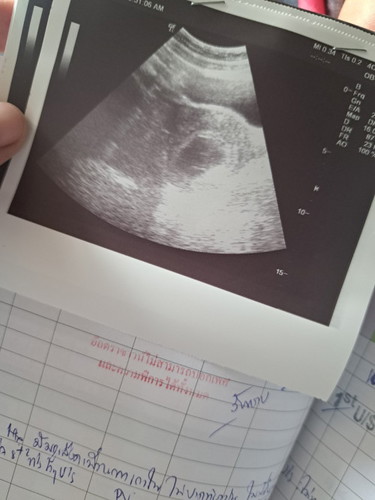

ท้องลม 9w5d

ตอนนี้น้องไม่โตแล้วค่ะ คุณหมอฟันธงว่าท้องลม100% เพราะถุงตั้งครรภ์ไม่โต ไม่มีตัวเด็ก แม่มีเลือดไหลตลอด หมอบอกตอนนี้มดลูกกำลังขับออกมาค่ะ